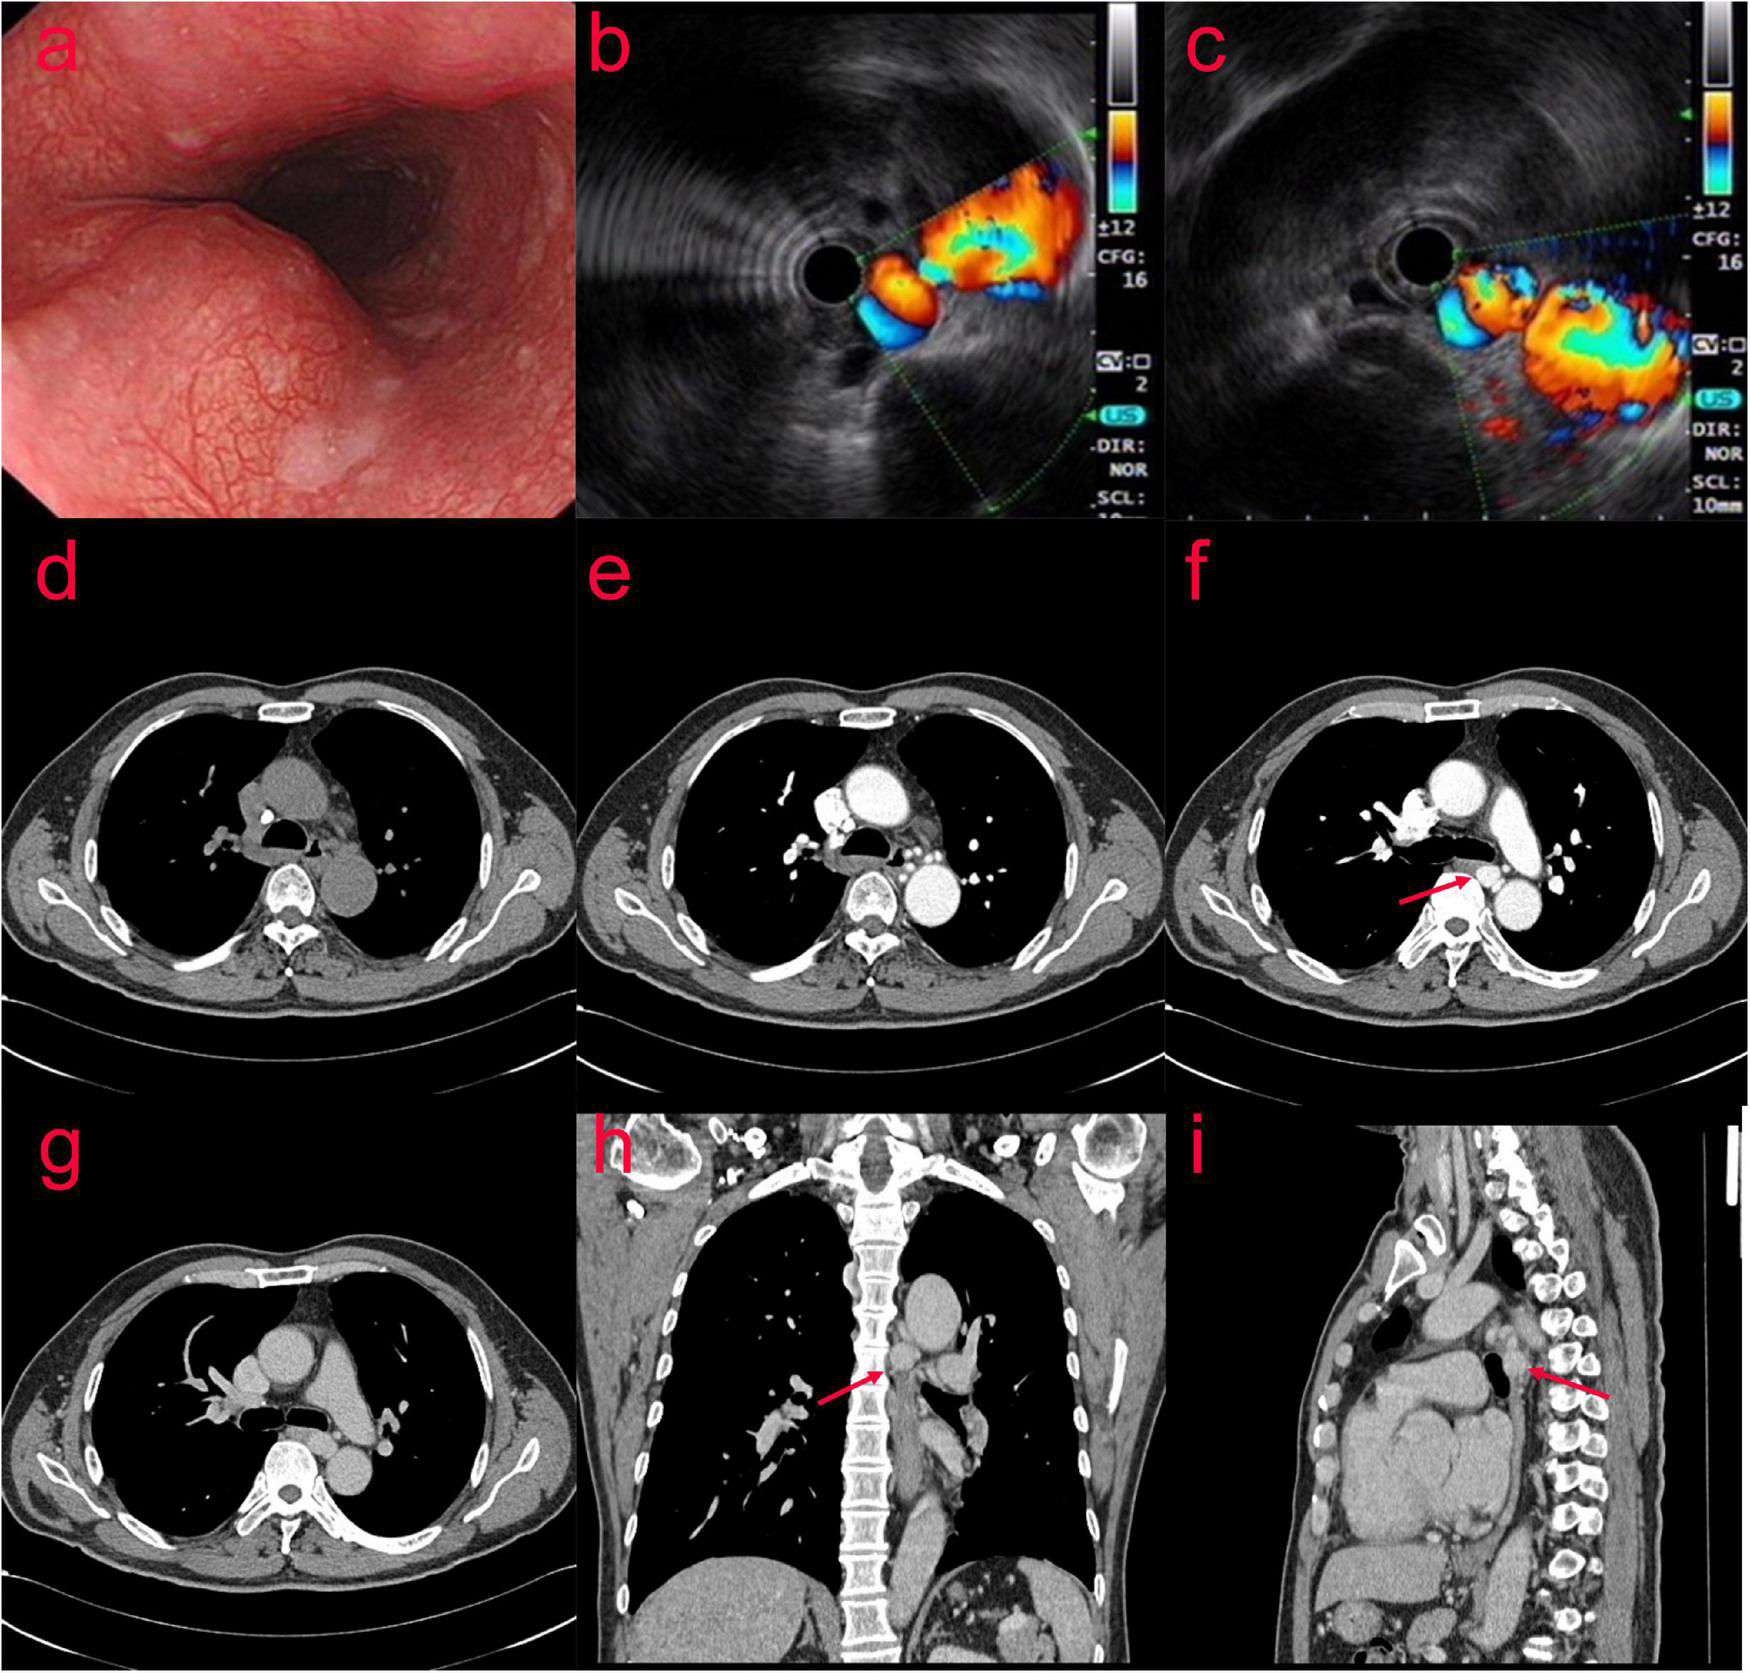

In July 2020, a 63-year-old man presented with recurrent chronic productive cough for more than 40 years prior to admission, occasionally with blood in the sputum. The patient was asymptomatic for dyspnea, dysphagia, or hemoptysis, and denied previous thoracic trauma. Plain chest computed tomography (CT) scan was performed due to cough and shortness of breath with the following findings: bronchiectasis with infection in the middle lobe of the right lung, the lingual segment of the upper lobe, and the lower lobe of the left lung. The patient was examined by gastroscopy (Figure 1a) at the local hospital, which showed an “esophageal mass.” Then, the patient visited our hospital, and ultrasonic gastroscopy showed an esophageal bulge, vascular compression, and suspected BAA (Figures 1b,c). A contrast-enhanced CT scan showed multiple tortuous and thickened vascular shadows, partial aneurysmal dilation (maximum width about 1.3 cm), vaguely connected with the thoracic aorta and left pulmonary vein, and adjacent esophageal compression. Partial bronchiectasis in both lungs with a small amount of inflammation (Figures 1d–i).

FIGURE 1

(Case one) The patient with Bronchial artery aneurysm (BAA) was examined by gastroscopy (a) at the local hospital, which showed an “esophageal mass.” After visiting our hospital, ultrasonic gastroscopy showed an esophageal bulge, vascular compression, and suspected BAA (b,c). A contrast-enhanced CT scan showed multiple tortuous and thickened vascular shadows (maximum width about 1.3 cm) in the middle and posterior mediastinum and around the esophagus (d–i).